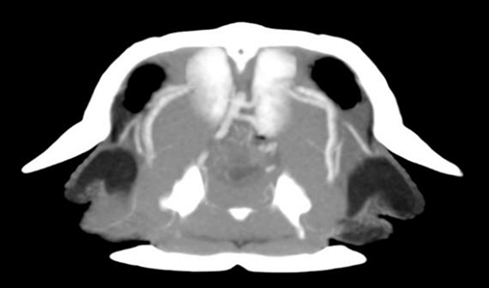

循環器系(心臓)

右-左シャント(R-L Shunt)

爬虫類は血液の流れる方向を生理的に制御することが可能です。通常、酸素化された血液は動脈洞から全身へ、脱酸素化された血液は静脈洞から肺洞を経て肺へと送られます。しかし、潜水時以外にでも麻酔による呼吸抑制時などの肺血管抵抗(Pulmonary Vascular Resistance: PVR)が増大する状況下では、肺動脈への血流が制限され、脱酸素化された血液が肺をバイパスして直接大動脈(体循環)へと流れる右-左シャントが発生します。これは臨床的に吸入麻酔の無効化が起こります。イソフルランやセボフルランなどの吸入麻酔薬は肺胞で血液に取り込まれる必要があります。しかし、右-左シャントが発生すると、血液が肺胞を通過しないため、麻酔ガスが血流に乗らず、脳へ到達しません。その結果、マスク導入を行っても麻酔がかかるまでに極めて長い時間を要するか、あるいは導入不能となりますか〔Scarabelli et al.2022〕。なお、シャントは非潜水時以外では、特に迷走神経の刺激などにより肺血管抵抗が上昇した際に発生します〔Bueggen 1987〕 。具体的には、強制的な保定、体温上昇〔Hicks 2002〕、行動上での自発的な呼吸停止〔Hicks 2002〕、外部からの脅威(捕食者の接近など)に遭遇した際のすくみ行動〔Saito et al.2022, Hicks et al.1996〕、乾燥、低温、飢餓などの環境ストレスに適応するための休眠や冬眠〔Leite et al.2014〕で発生します。特にワニ類や大型のヘビにおいては、二酸化炭素(CO2)の有効利用のために存在することも示唆されています。胃で食物を消化する際、胃壁細胞は大量のプロトン(H+)を分泌して塩酸(HCl)を生成します。このH+は、血液中のCO2と水から炭酸脱水酵素の作用によって生成されます。この過程で副産物として生成される重炭酸イオン(HCO3-)は血中へ放出されるため、食後の血液pHは上昇(アルカリ化)します。このアルカリ化を中和し、かつ胃酸生成の原料となるH+を持続的に供給するためには、大量のCO2が必要となるため、シャントが決定的な役割を果たします〔Farmer et al.2008〕。以上の包括的な分析により、爬虫類の右左心内シャントは、従来考えられていたような潜水への適応あるいは不完全な循環系という枠組みを遥かに超えた、多機能かつ洗練された生理学的システムであることが明らかとなりました。